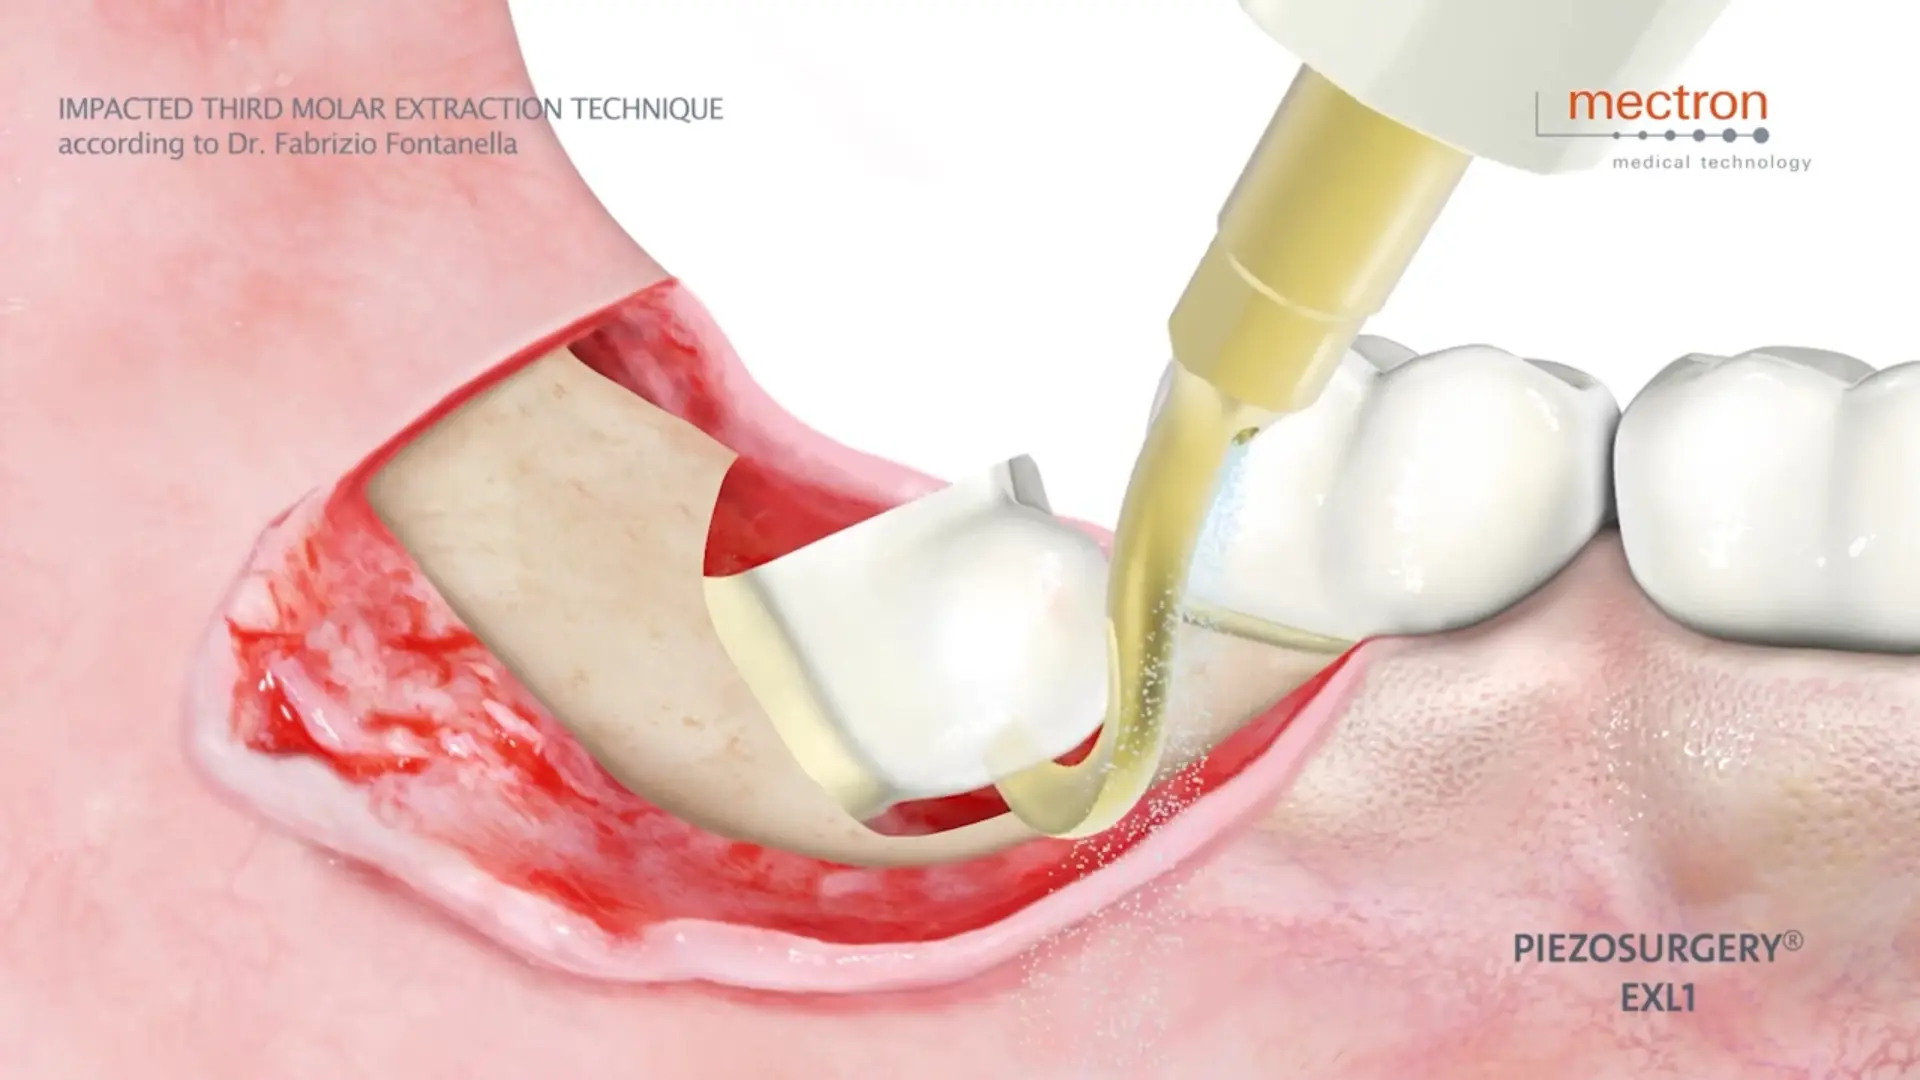

Dr. Fabrizio Fontanella

Impacted third molar extraction technique

Dr. Fabrizio Fontanella